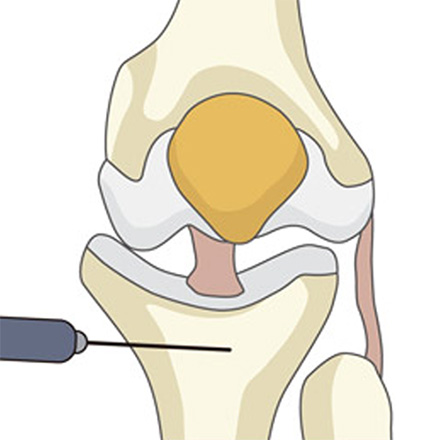

정강이뼈(경골) 윗부분을 약 3~5cm 절개한 뒤, 정강이뼈에 금을 냅니다.

-